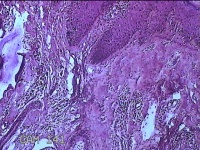

头部肿物

性别

男

年龄

21岁

临床诊断

头皮肿物

一般病史

发现头部结节10余年,无明显疼痛及不适。

标本名称

头部结节

大体所见

灰白暗红色带皮肤样结节1.5x1.3x0.3cm一个,切开结节呈实性,切面灰白粉红色,质软。